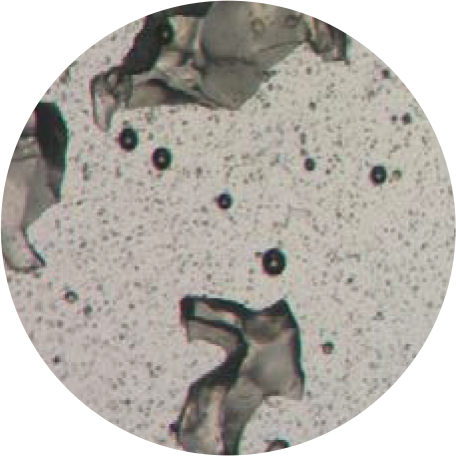

EL GEL SE SOMETE A UN PROCESO PROPIETARIO DE MOLIENDA HÚMEDA, RESULTANDO EN PARTÍCULAS ESFÉRICAS.

Las partículas esféricas suelen tener menos área superficial. Las reacciones inflamatorias son más pronunciadas para partículas de forma irregular o aquellas con mayor área superficial.

Partículas de HA suaves, esféricas y uniformes.

Las partículas suaves y esféricas promueven una mejor integración en los tejidos y se ha demostrado que reducen el riesgo de desencadenar una reacción de cuerpo extraño.